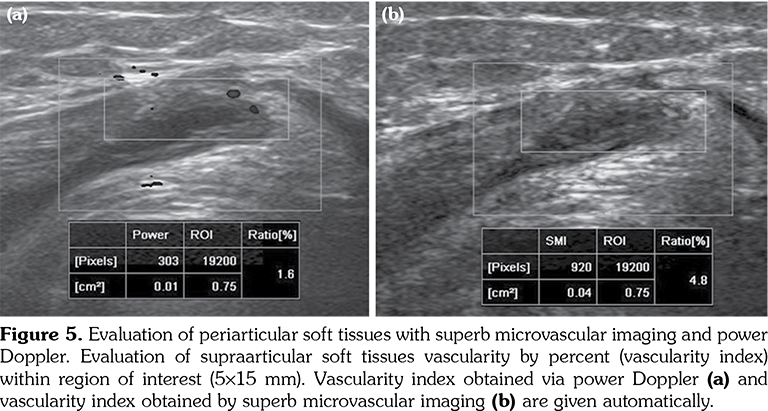

All patients and healthy volunteers were screened with Canon Aplio 500 Platinum US device (Canon Medical Systems, Tokyo, Japan) equipped with SMI, PD and SWE functions. All participants were examined in supine position and their knees were in extension (Figures 1, 2). Once the gray scale US examination confirmed the arthritis based on synovial thickening, joint effusion and periarticular echogenicity, then SMI and SWE were performed to the supraarticular and infraarticular soft tissues concerning the synovium and periarticular soft tissues. VI is a novel parameter determined for SMI and PD corresponding the ratio of colored pixels to the total pixels within the selected region of interest (ROI). VI was calculated automatically on colored SMI and PD images over the selected rectangular shaped ROI with edges measured 5x15 mm (Figure 3). Mean VI values were calculated by averaging results of three different acquisitions of PD and SMI. The ROI was placed perpendicular to the long axis of the knee joint at the supraarticular and infraarticular locations including the synovium and periarticular soft tissues. On SWE evaluation, the QT and PT were demonstrated along with their long axis. Three different ROIs for SWE were performed from the tendon halves closer to the knee joints. Each ROI was in circle shape and 3 mm in diameter. We depicted mean elasticity for PT, QT, supraarticular soft tissues (SAST) and infraarticular soft tissues (IAST) (Figures 4, 5).

The mean SWE values obtained from SAST including synovium and suprapatellar fat pad was 10.7±2.5 kPa in study group and 9.9±2.3 kPa in the control group (p>0.05). The mean SWE values obtained from IAST including synovium and infraarticular fat pad was 9.8±2.4 kPa in study group and 9.4±2.3 kPa in the control group (p>0.05). No significant difference was found among SWE values of periarticular soft tissues among study and control subjects. The mean SWE of PT was 19.7±6.9 kPa in the study group and 16.5±4.8 kPa in the control group. Although the mean QT SWE (19±6.1 kPa) was higher in the study group than the control group (15.7±4.8 kPa), the differences among the mean SWE values of QT and PT failed to reach statistically significant levels (p>0.05) (Table 1).

Shear wave elastography is also called dynamic elastography and uses “acoustic radiation force sequence to generate shear waves propagating perpendicularly to the US beam”[21] causing tissue displacement. Changes in the shear wave velocities are associated with viscoelastic tissue properties and calculated based on the shear modulus that can be calculated by multiplying tissue density and square of the shear speed.[21] Shear waves propagate faster in stiffer tissues. The viscoelastic properties of tendons may be changed due to investigated tendon parts, duration of the inflammation or presence of joint contractures. The combined evaluation of periarticular soft tissues with color Doppler and SWE has been found to increase the diagnostic accuracy in terms of determining acute phase of gout from intercritical phase for the first metatarsophalangeal joints.[22] Although we have not found significant differences among mean SWE values, they were higher in the study group. Since normative tendon elasticity values have not been determined for children, serial measurements during follow-up may reveal chronicity and also support disease activity when combined with SMI.